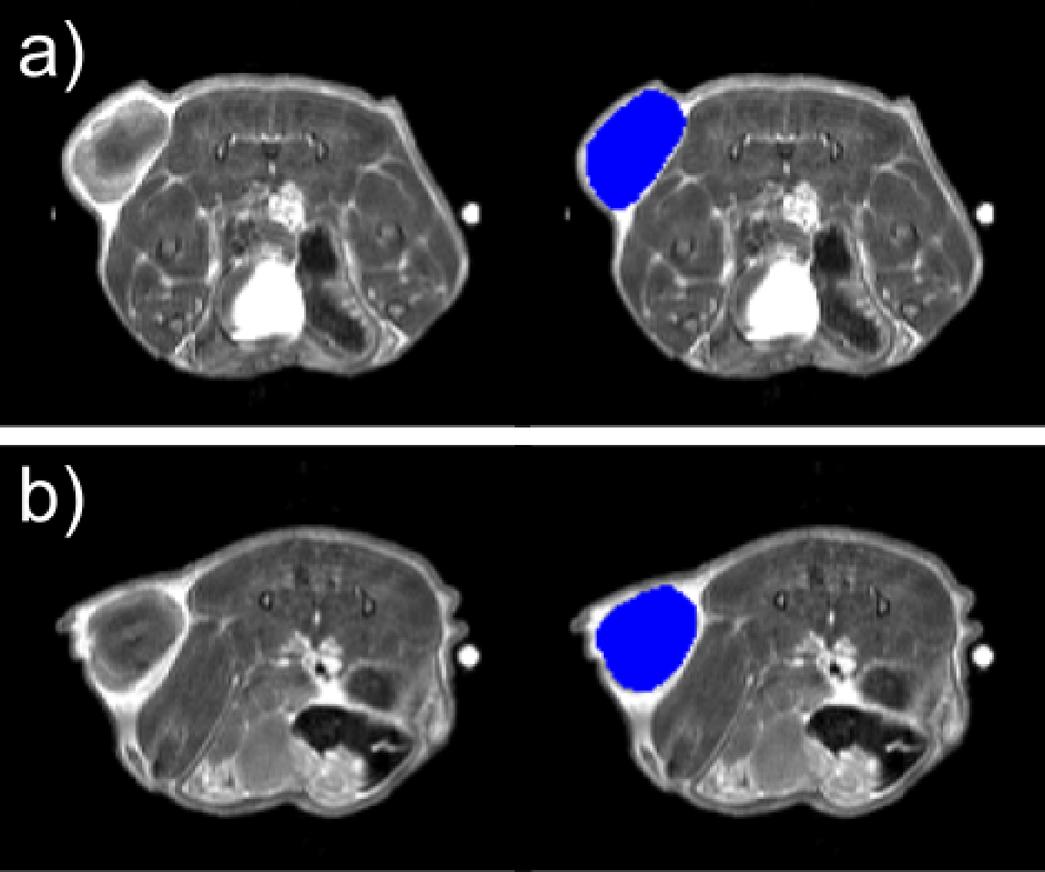

Fig. 2

A three-dimensional mask including the whole tumor was drawn before (Panel a) and after (Panel b) RFA treatment on axial 3D T2w RARE sequence.